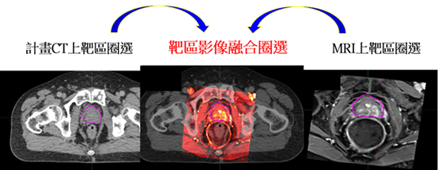

首先設計個人化之固定模具結合個人化腹部壓縮設備,進行4D電腦斷層攝影,必要時結合呼吸調控技術,進行治療前模擬。之後,將各式影像例如磁振照影、電腦斷層攝影與正子攝影等多種影像透過影像融合技術 ,精準定位出腫瘤位置 (圖二),同時醫師透過腫瘤靶區的圈選與透過人工智慧(Artificial Intelligence, AI)系統進行周遭正常組織之標定,與醫學物理師討論進行治療計畫設計,透過動態弧形技術給予腫瘤需的劑量、正常組織須限制的劑量,治療入射角度,治療入射方向等細節,來增加腫瘤精準治療包覆性與成功降低周遭正常組織劑量,來成功達到腫瘤消融與保護正常組織的目的。(圖三)

圖二、透過影像融合技術, 增加靶區精準度